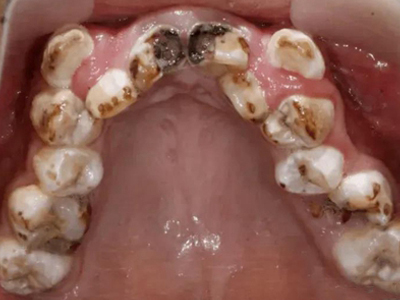

酸蚀症牙齿缺损不平整图

酸蚀症患者的牙齿会发生缺损,轻度时仅表现为牙齿尖端凹凸不平,有少量骨质缺失,缺损处有黄褐色至红褐色斑点,该病可能是长期接触外源性酸性物质而致病。

酸蚀症牙齿多处缺损发黄图

酸蚀症患者的牙齿会出现多处缺损,牙根部有不规则骨质剥脱,周围发黄,牙前侧也出现坑洼及大块缺损,使牙列不平整,可进行脱敏、修复治疗等。

酸蚀症后排牙齿大量缺损图

酸蚀症患者的后排牙齿可发生大量缺损,一侧牙齿遗留圆盘状牙根,形似被切割,另一侧牙齿有大量凹陷坑洞,部分牙齿颜色发黑或呈黄褐色,其发生与长期接触酸性物质有关。